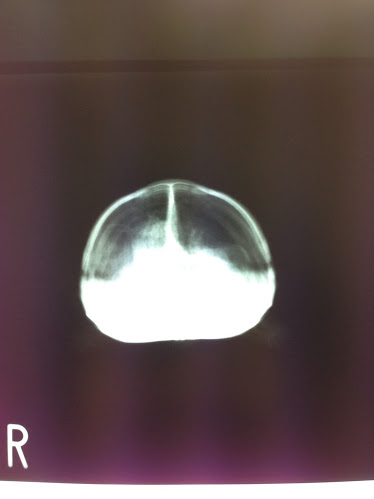

上:横から見たところ(左が頭)、下:正面から見たところ

素人目に見ても嫌な感じがしました。

ハッピーのときのレントゲン写真とは違い、白い部分が多いです。

先生の話を聞くとどうやら肺炎ではないらしい。

しかし気管支炎との診断が・・・

どうも、気管支炎のため空気が肺に100%入らずに胃などへ流れて溜まってしまっているみたいです。

写真の左側の白い面積が広いと思いますが、ここにガスが溜まっているみたいです。

100%の空気が肺に入らないためさぞ苦しかったと思います。